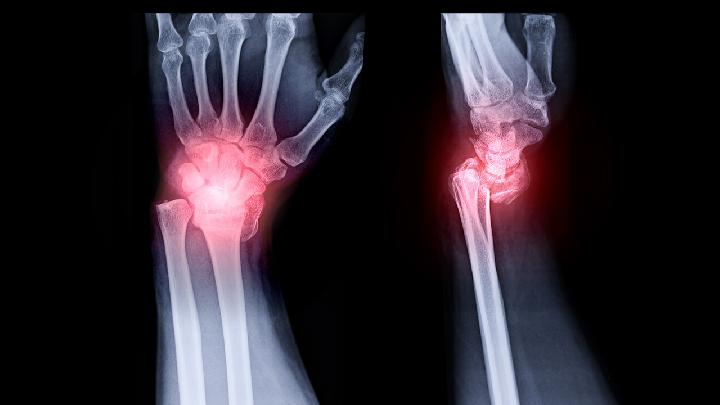

手指腱鞘炎常发生在手指的掌面,每一手掌面的肌腱都有一鞘,当腱鞘受伤破损而使细菌侵入鞘内,就会发生腱鞘炎。致病菌多为金黄色葡萄球菌,手指腱鞘炎多因刺伤、挫伤、倒刺或剪指甲过深等损伤而引起。

腱鞘具有维持手指的正常屈伸和肌腱滑动的功能。当手部固定在一定位置作重复、过度活动时,使肌腱和腱鞘之间经常发生摩擦,以致水肿、纤维性变,引起内腔狭窄。由于肌腱在腱鞘内活动时,通过的径道狭窄,从而出现疼痛和运动障碍,这就是手指腱鞘炎,或者叫节活动障碍。常发生在手指的掌面,患指出现红、肿、痛、热征象,呈屈曲状,因为手指伸直就会引起疼痛。

腱鞘是包绕肌腱的鞘状结构,当腱鞘内层反复过度摩擦,就会引起腱鞘及肌腱发生炎症、水肿,纤维鞘壁增厚而形成狭窄环,由于肌腱在腱鞘内活动时,通过的径道狭窄,从而出现疼痛和运动障碍,这就是腱鞘炎。以下这些动作可以有效预防腱鞘炎: